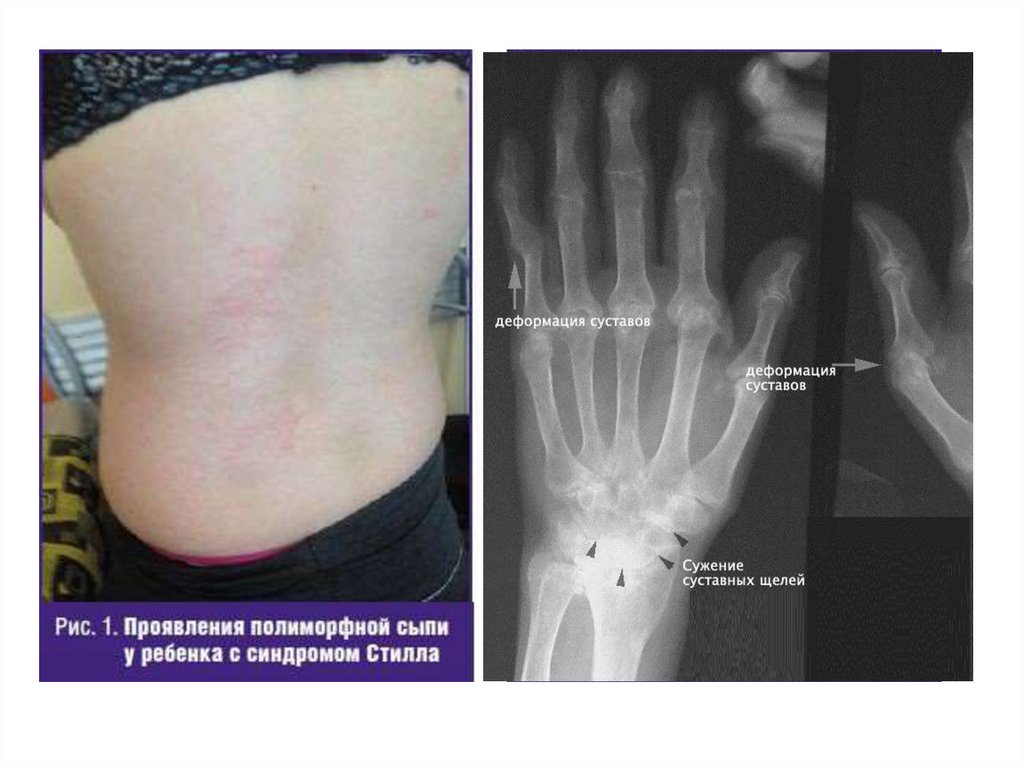

•Саусақаралық, білезік, шынтақ

буындарында ісіну,

Рентгенде: эпифизарлы остеопороз, буын

саңылауының тарылуы.